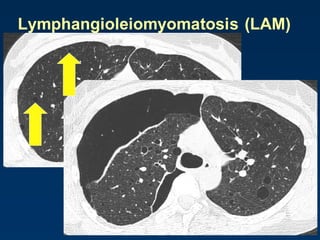

Lymphangioleiomyomatosis (LAM)

HRCT Morphology

Thin-walled cysts (2mm - 5cm)

Uniform in size / rarely confluent

Homogeneous distribution

Chylous pleural effusion

Lymphadenopathy

in young women

Tuberous Sclerosis (young man)